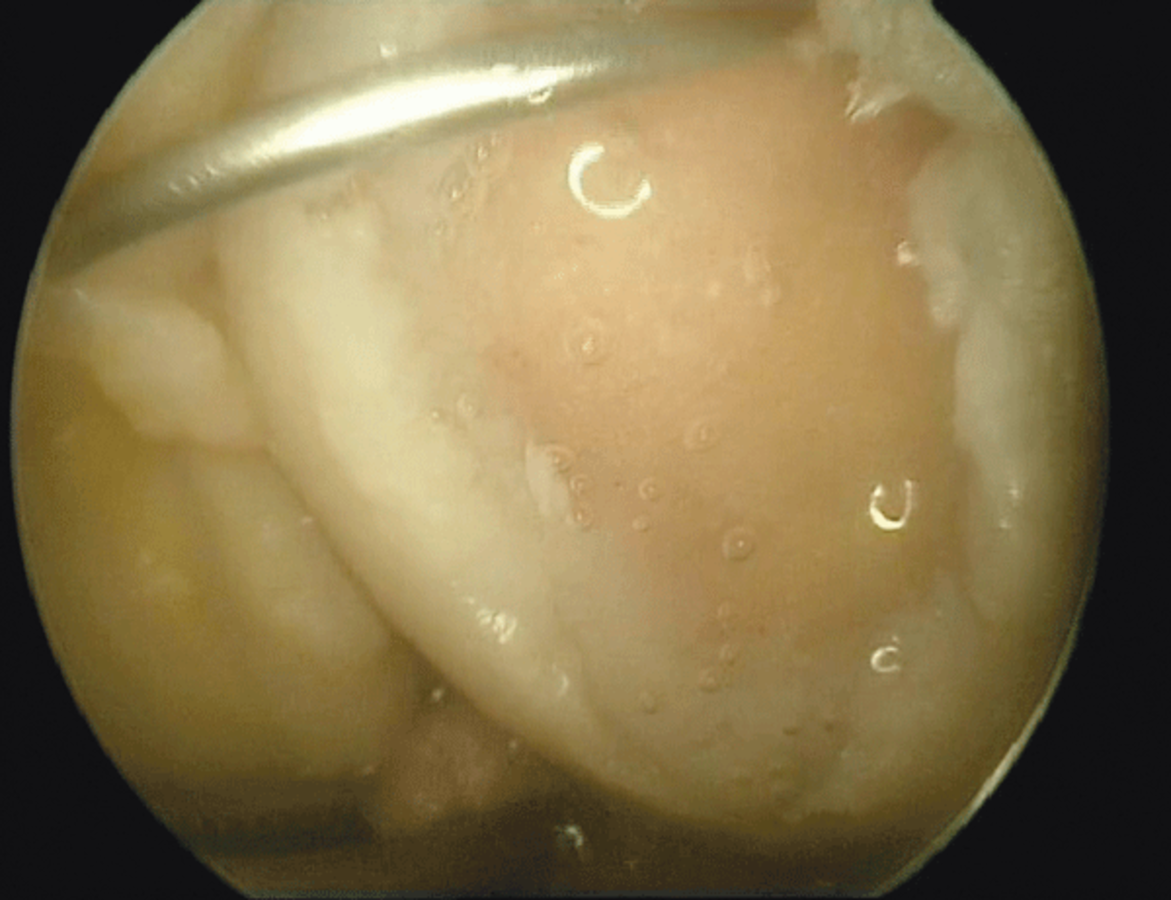

Ist die Gelenkmaus verloren gegangen und liegt ein tiefer Knorpelknochendefekt vor, kann dieser chirurgisch mit einem Knorpelersatzstoff behandelt werden. Ist die Gelenkmaus verloren gegangen und liegt ein tiefer Knorpelknochendefekt vor, kann dieser chirurgisch mit einem Knorpelersatzstoff behandelt werden. © Jerosch J. internistische praxis 2018; 59: 253-272; © Mediengruppe Oberfranken – Fachverlage GmbH & Co. KG, Kulmbach